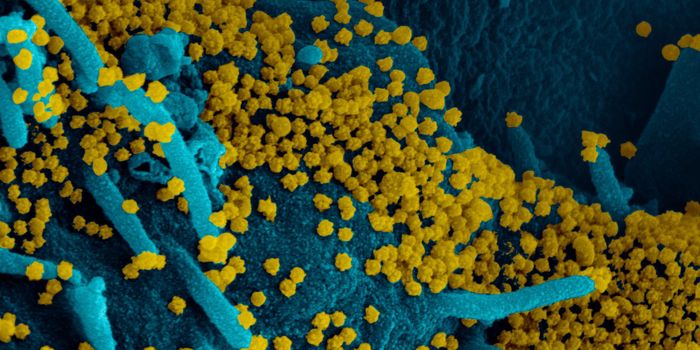

JUL 05, 2020Cell & Molecular BiologyThe pandemic virus SARS-CoV-2 enters the body through the respiratory system to cause the illness COVID-19. But we know ...

MAR 18, 2020MicrobiologySARS-CoV-2 is a coronavirus that causes an illness called COVID-19. There are now well over 210,000 confirmed cases worl ...

APR 06, 2020Genetics & GenomicsSARS-CoV-2 is the name for the pandemic coronavirus that causes the illness COVID-19, which affects people in extremely ...